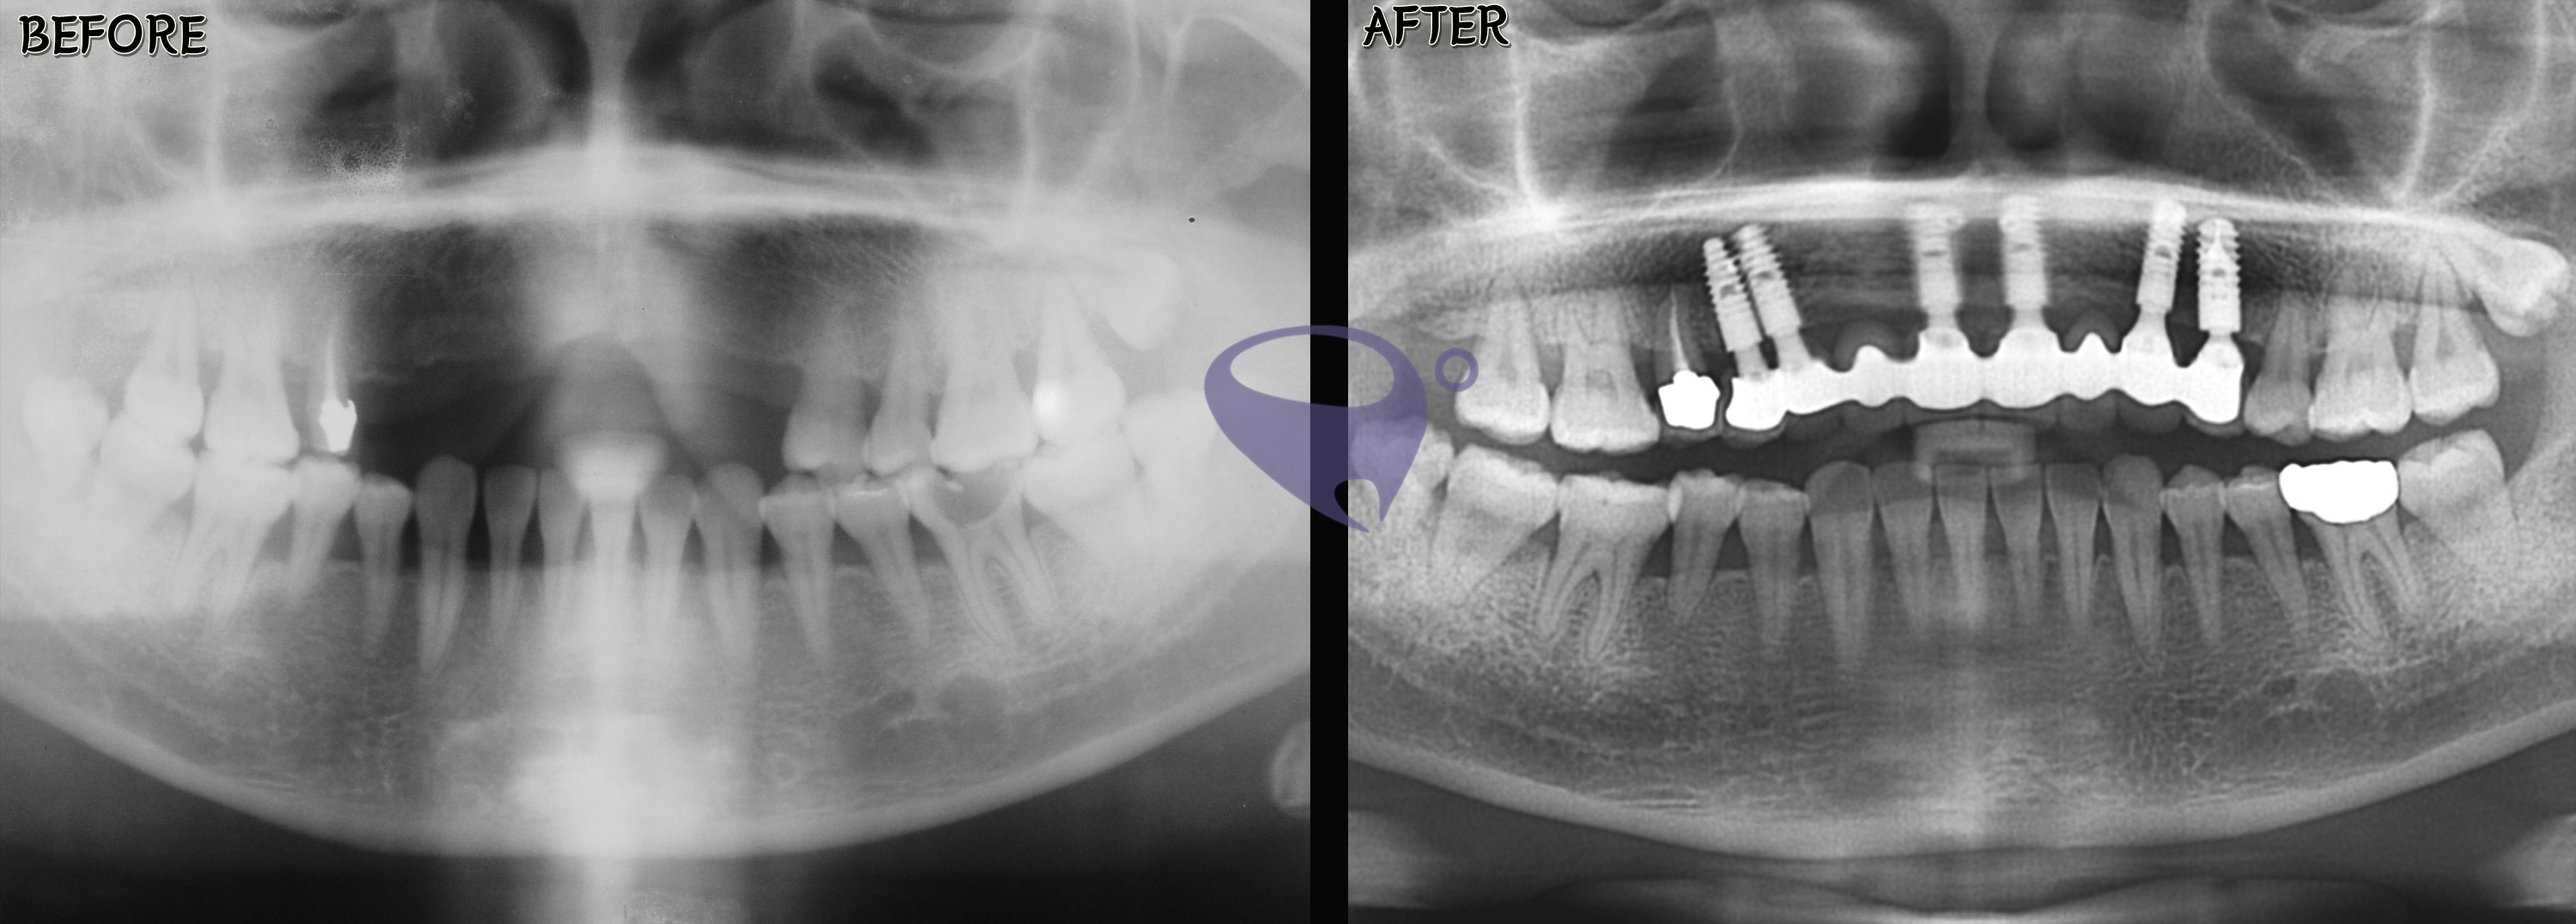

请参考我们PARK AVENUE牙科实际 #治疗事例 。